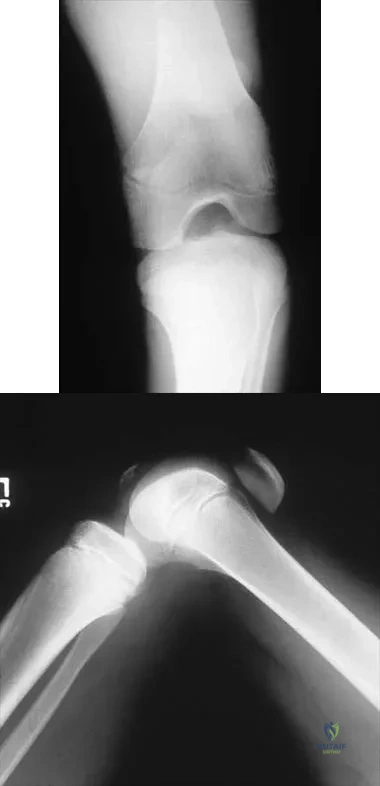

Figure 53a shows the AP radiograph of a 70-year-old patient who is scheduled to undergo unicompartmental knee arthroplasty. Figure 53b shows the immediate postoperative radiograph, and the radiograph shown in Figure 53c, obtained 6 months after surgery, shows a medial tibial plateau fracture. The etiology of the fracture is best related to